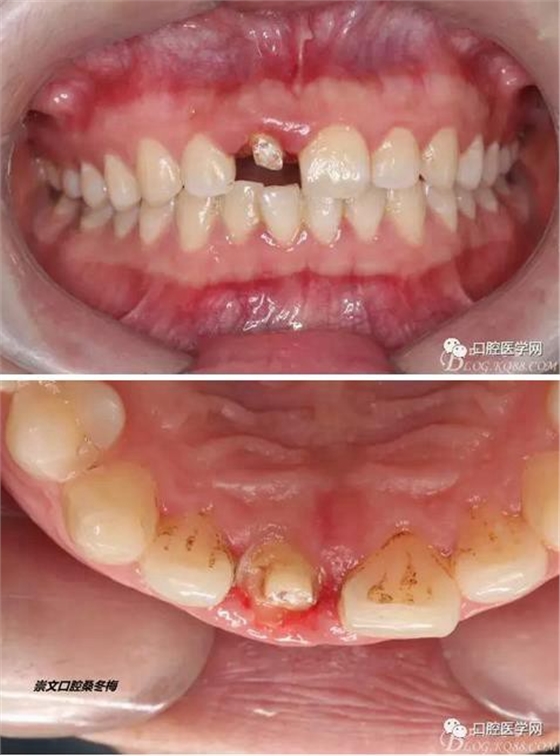

術(shù)前口內(nèi)照,11殘根,唇側(cè)牙齦紅腫,肩臺(tái)在齦下2毫米,舌側(cè)正常.21有被動(dòng)萌出,長(zhǎng)寬比例不協(xié)調(diào)??谇恍l(wèi)生一般,有菌斑。

術(shù)前原有牙冠復(fù)位,牙齦紅腫。